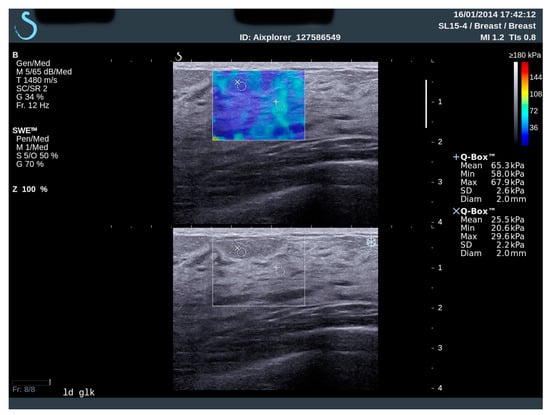

2.2. Elastography and Analysis